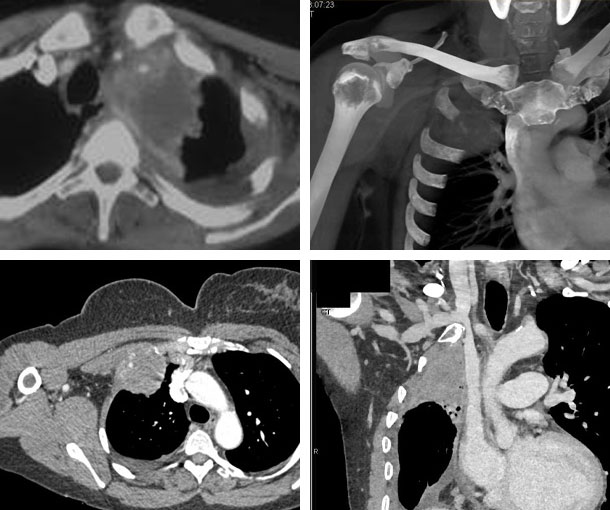

Pancoast Tumor CT Findings

- Pleural thickening

- Asymmetry of the apical cap(s) > 5mm

- Bone destruction

- May invade the thoracic wall or spine